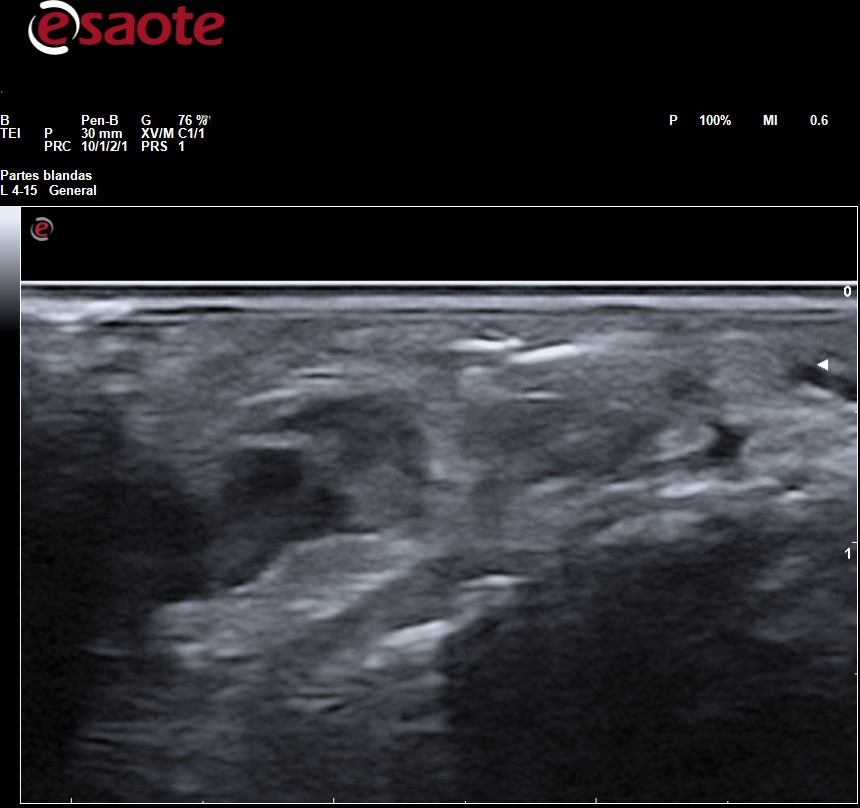

Observamos en el tejido celular subcutáneo imagen lineal hiperecogénica con artefacto de reverberación

La Rx es la primera técnica de diagnóstico para identificar y localizar cuerpos extraños, sin embargo, en ella solo pueden apreciarse la presencia de fragmentos radiopacos (metal, vidrio, piedra y algunos plásticos). Los fragmentos de madera, espinas de plantas y de pescados son indetectables. La Rx da una idea de la ubicación del fragmento y de sus relaciones con huesos y articulaciones adyacentes, pero no puede determinarse la ubicación del fragmento con relación a las estructuras adyacentes: tendones, vasos sanguíneos y nervios que sí podremos determinar con precisión mediante la ecografía lo cual facilita la planificación para su extirpación. Tanto los fragmentos radiopacos como los radiotransparentes se aprecian en ecografía como imagen hiperecogénica con artefacto de sombra acústica posterior o de reverberación según las características del cuerpo extraño rodeada de halo hipo-anecoico si hay granuloma.